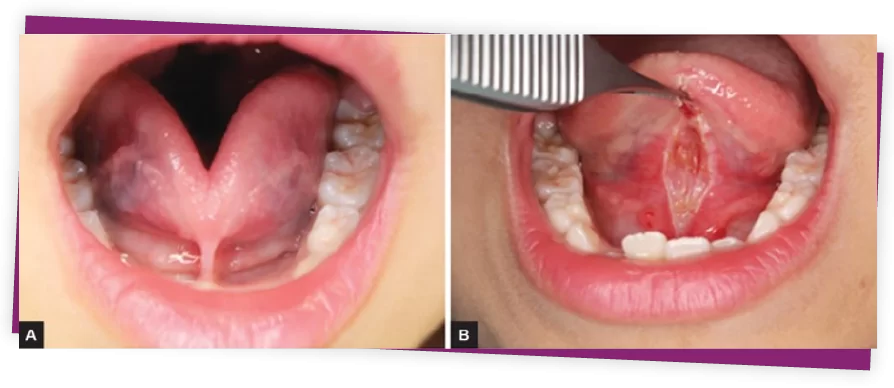

Phẫu thuật cắt thắng lưỡi.